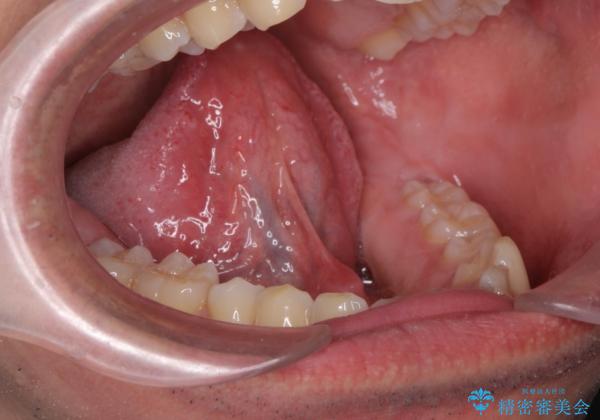

[ 舌小帯の形成術 ] ラ行の発音を改善したい

- 「ラ行の発音がしづらい、改善したい。」、と舌小帯の形成の相談に来られました。

形成術を行うことで、滑舌の改善が見込めることから即日で舌小帯の形成術を行うこととしました。

術後、「かなり発音がしやすくなりました。」

と治療結果に喜んでいただくことができました。